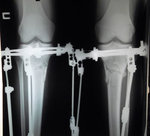

Дата операции 16.10.2014г.

Дата снятия аппаратов 30.01.2015г.

Срок лечения 102 дня.

Добрый день, Наталья.

Как ваши дела? У меня все отлично. Потихочнеку воостанавливаюсь. Одеваю юбки, платья и до сих пор не могу поверить что, это я и мои ножки!

Какое же это непередаваемое чувство, когда ты ходишь по магазинам и не проходишь как раньше мимо стеллажей с короткими юбками и платьями!

Вот прошло 1,5 месяца и как требуется сделала рентген, высылаю его. Передавайте Николаю Николаевичу большой привет и слова благодарности от меня!